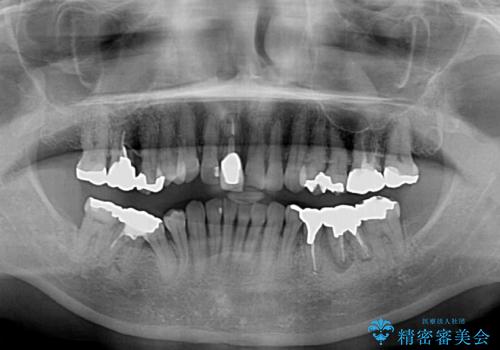

- 口腔内にある銀歯を全て外したいとのことで来院された患者様です。

土台に含まれている金属も含め、口腔内の金属は全て除去し、抜歯しなければならない歯は抜歯し、オールセラミッククラウンやセラミックインレーにて治療することとしました。

上下奥歯の抜歯を同時期に行わず、下顎の治療を終えてから上顎を抜歯して治療を進めたため、1年ほどの期間を要しました。